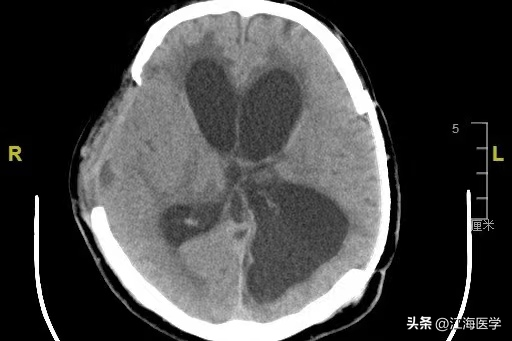

忙碌的义诊结束后,上海冬雷脑科医院神经外科主诊专家、神经血管外科学术中心主任、神经解剖实验中心主任王威又马不停蹄地赶到手术室,为一名51岁的男性脑积水患者施行了腰大池-腹腔分流示教手术。